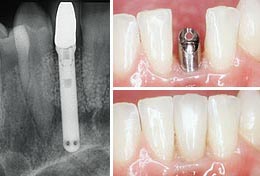

Имплантация — это операция по внедрению в организм специальной структуры с целью замещения и восстановления утраченного органа и его функции. В стоматологии имплантат — это элемент ортопедической конструкции, изготовленный из химически чистого титана, как правило, имеет форму винта различного дизайна, и устанавливается в костную ткань челюсти. По своей сути имплантат — это протез корня. Он замещает собой потерянный зуб и является опорой для ортопедической коронки.

Процесс восстановления удаленного зуба с использованием имплантатов состоит из нескольких этапов.

Показаниями для имплантации является отсутствие одного, нескольких подряд или всех зубов.

В нашей клинике используются самые современные имплантаты от ведущих мировых компаний.

Через 6 месяцев на прицельных снимках и компьютерной томограмме отмечается полное заживление костной ткани, губчатого и кортикального слоя.